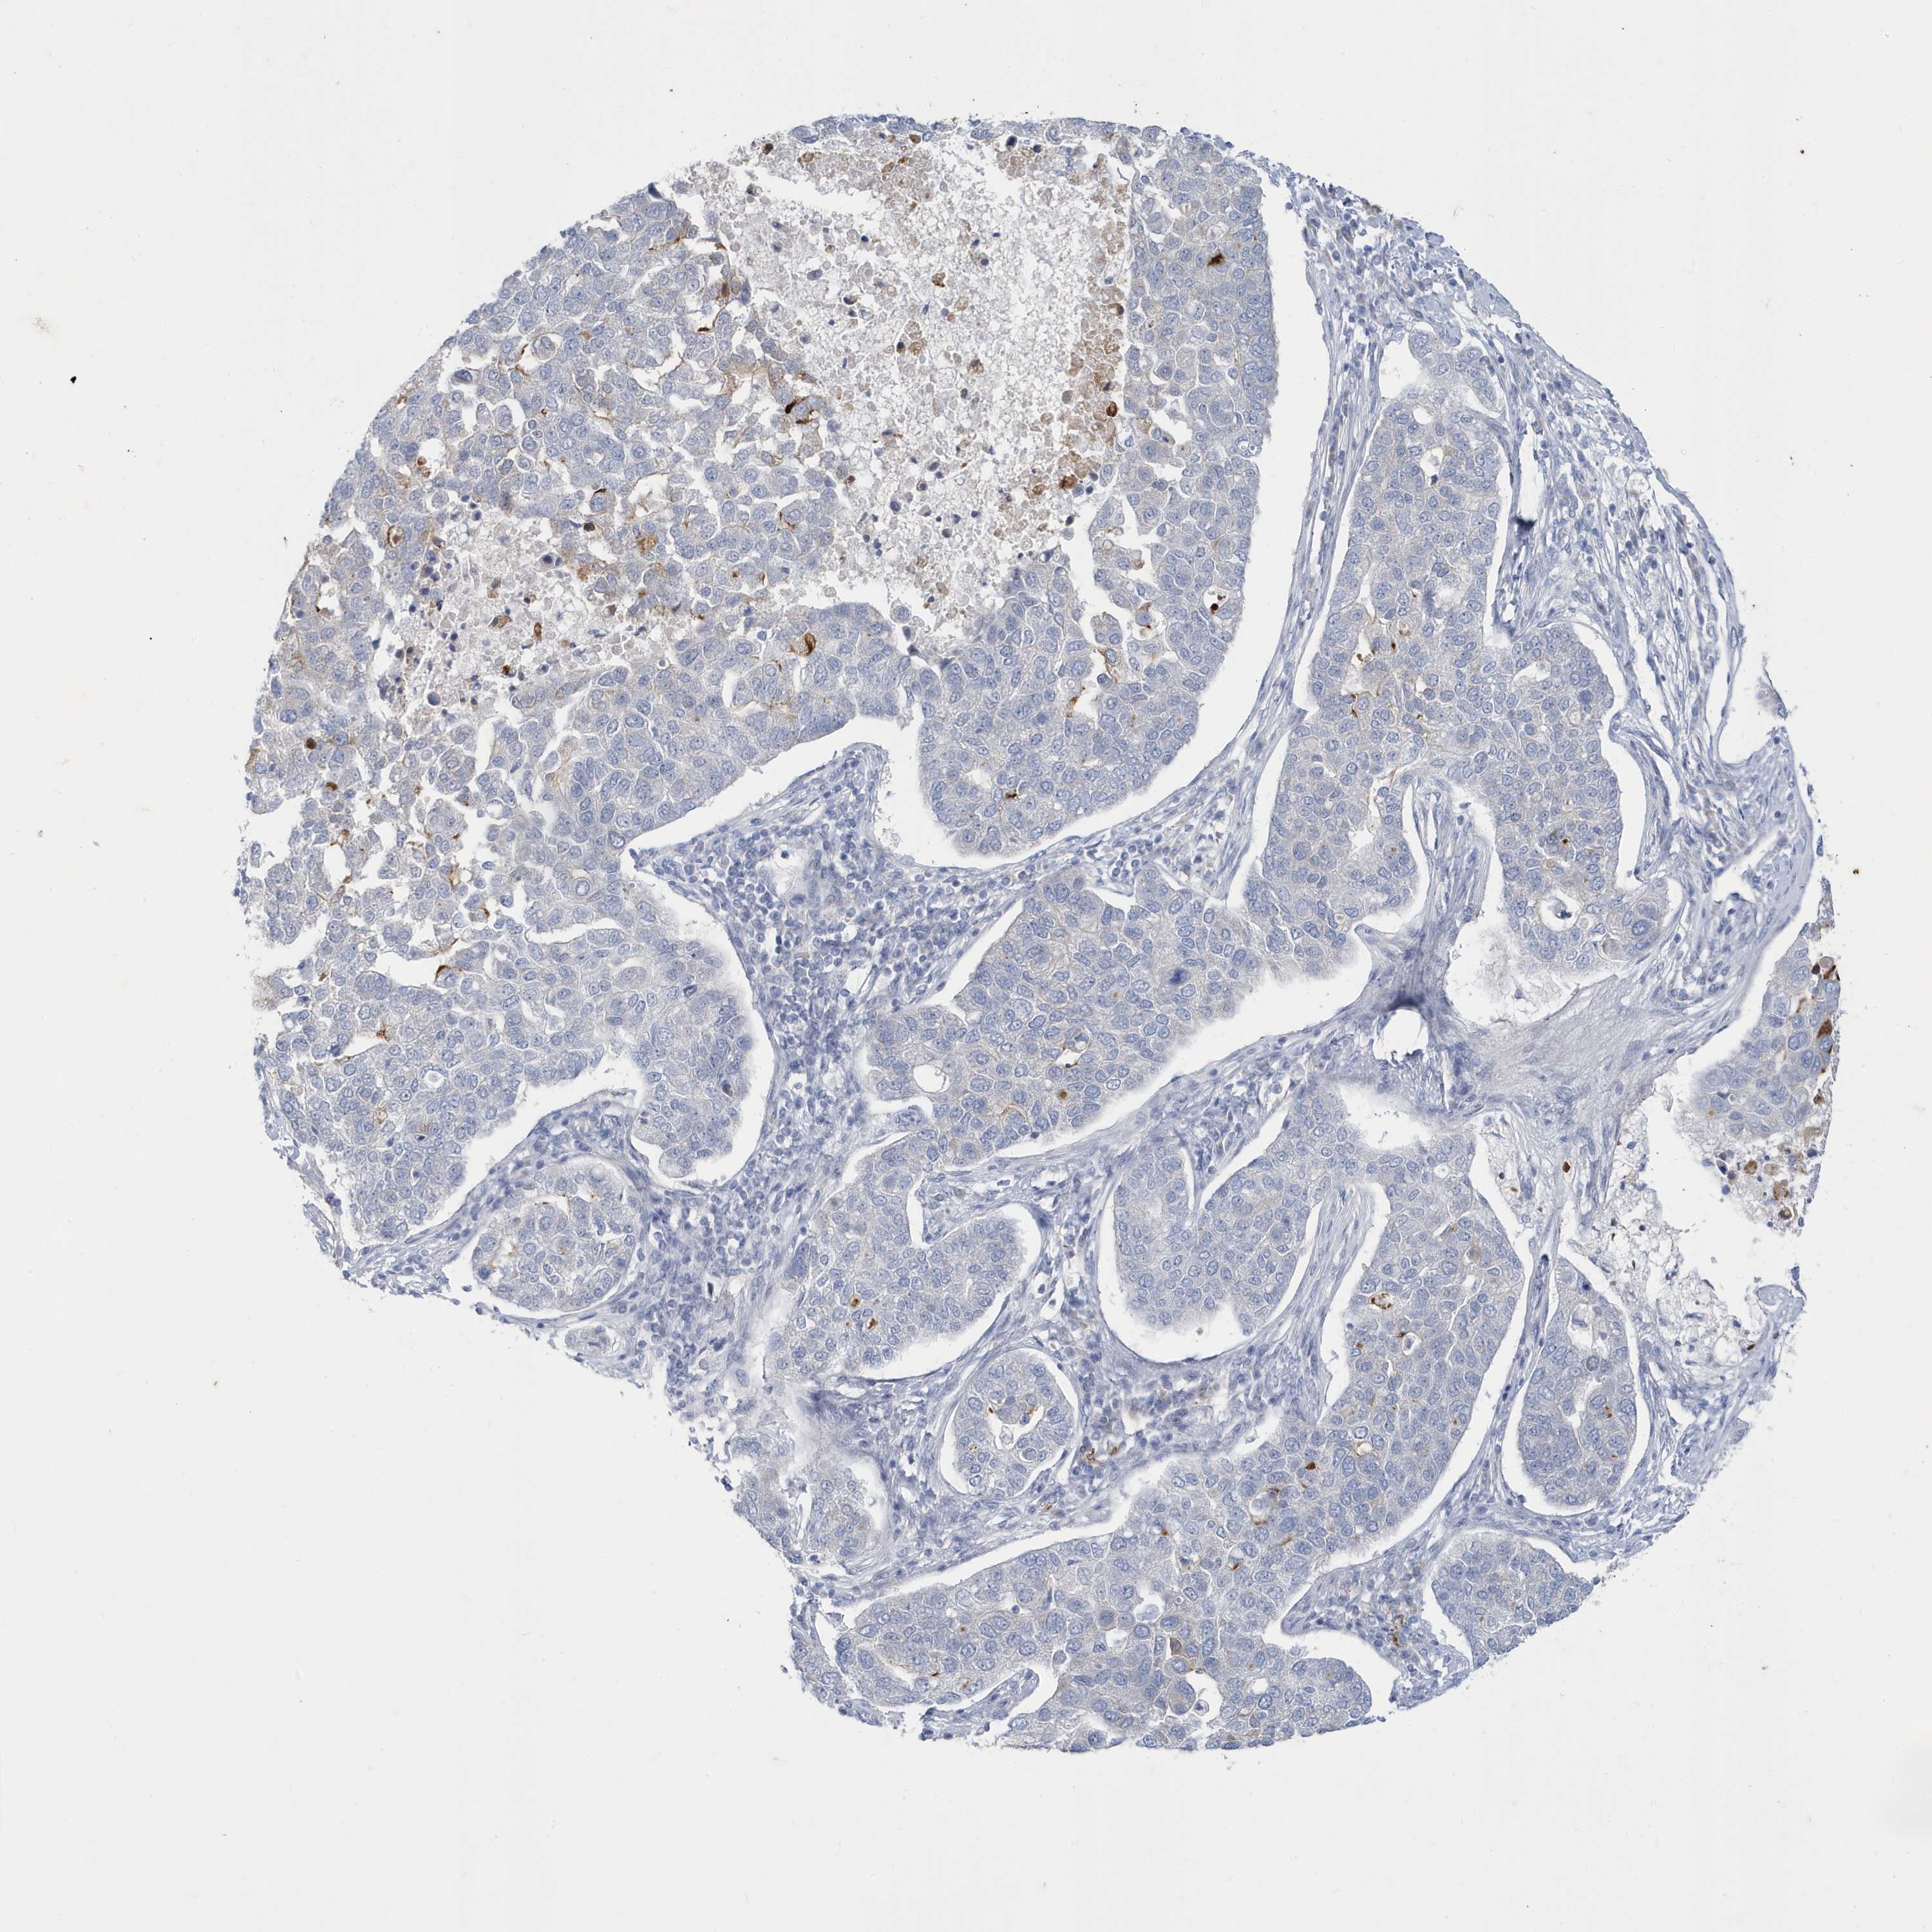

PANCREATIC CANCER - Protein expressioni

A mouse-over function shows sample information and annotation data. Click on an image to view it in a full screen mode. Samples can be filtered based on level of antibody staining by selecting one or several of the following categories: high, medium, low and not detected. The assay and annotation is described here.

Note that samples used for immunohistochemistry by the Human Protein Atlas do not correspond to samples in the TCGA dataset.

Antibody stainingi

Antibody staining in the annotated cell types in the current human tissue is reported as not detected, low, medium, or high, based on conventional immunohistochemistry profiling in selected tissues. This score is based on the combination of the staining intensity and fraction of stained cells.

Each image is clickable and will lead to virtual microscopy that enables deeper exploration of all samples and also displays staining intensity scores, fraction scores and subcellular localization as well as patient and tissue information for each sample.

Antibody HPA036172

Antibody HPA036173

Antibody HPA049262

Staining

High

Medium

Low

Not detected

Intensity

Strong

Moderate

Weak

Negative

Quantity

>75%

75%-25%

<25%

None

Location

Nuclear

Cytoplasmic/membranous

Cytoplasmic/membranous,nuclear

Adenocarcinoma, NOS